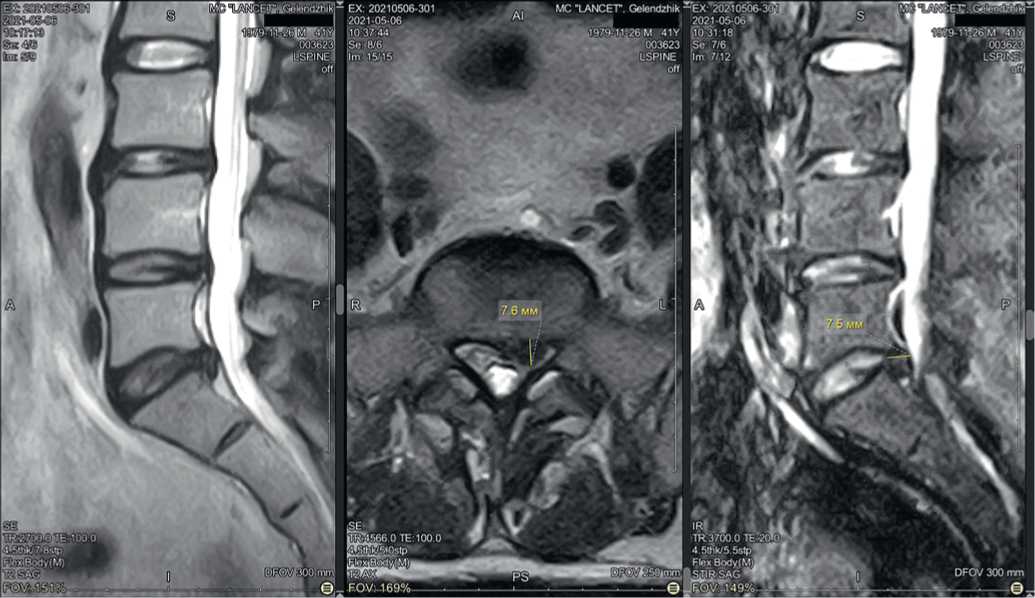

Пациент И., 41 года, обратился в Центр китайской медицины «Синь-я-Чжу» 09.09.2020 с жалобами на постоянную тянущую боль в пояснице с иррадиацией в левую нижнюю конечность. Резкий болевой синдром пациент отмечал даже при легком наклоне вперед, при попытке встать со стула и при ходьбе.

При МРТ от 09.09.2020 обнаружена грыжа диска L5–S1 размером 6,2 мм, отечность окружающих тканей (рис. 6).

Рис. 6. Исходная магнитно-резонансная томограмма пациента И. при обращении 09.09.2020: A) саггитальные срезы, B) аксиальные срезы на уровне межпозвонкового диска L5–S1

После курса акупунктуры болевой синдром купирован. При контрольной МРТ от 28.12.2020 отмечено уменьшение грыжевого выпячивания до 5,3 мм (рис. 7).

Рис. 7. Контрольная магнитно-резонансная томограмма пациента И. после курса акупунктуры 28.12.2020: A) саггитальный срез, B) аксиальный срез на уровне межпозвонкового диска L5-S1

Fig. 7. Control magnetic resonance imaging of patient I. after acupuncture course on 28.12.2020: A) saggital slice, B) axial slice at the level of intervertebral disc L5-S1

В дальнейшем пациент И. «для закрепления успеха» в течение 5 месяцев получал лечебные процедуры у кинезиотерапевта и остеопата, однако эффект получился обратным: вновь появились боли с тенденцией к интенсификации, пациент не мог стоять, сидеть и ходить. Трижды проведены анестезирующие блокады — без эффекта. При МРТ от 06.05.2021 выявлена парамедианная грыжа L5–S1 размером 7,8 мм (рис. 8).

Рис. 8. Магнитно-резонансная томограмма пациента И. при повторном обращении 06.05.2021: A) саггитальный срез, B) аксиальный срез на уровне межпозвонкового диска L5-S1, C) еще один саггитальный срез

Fig. 8. Magnetic resonance imaging of patient I. upon return visit on 05.06.2021: A) sagittal section, B) axial section at the level of the intervertebral disc L5-S1, C) another sagittal section